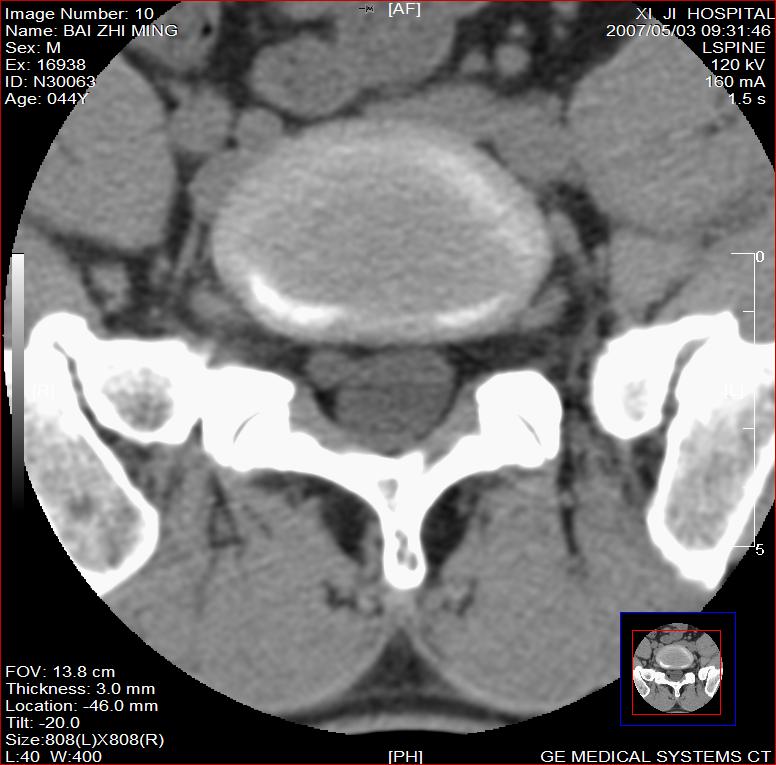

标题: CT8228:男,44岁,腰痛3月,加重3天,这是正常的吗?

男,44岁,腰痛3月,加重3天。

同意2楼,左侧神经根增粗,欠规整,神经根炎或神经源性肿瘤可能,建议mri检查。

左侧神经根增大.并硬脊膜囊受压(1,神经根炎2神经根肿瘤)

左侧神经根增粗,欠规整,神经根炎或神经源性肿瘤可能,建议mri检查